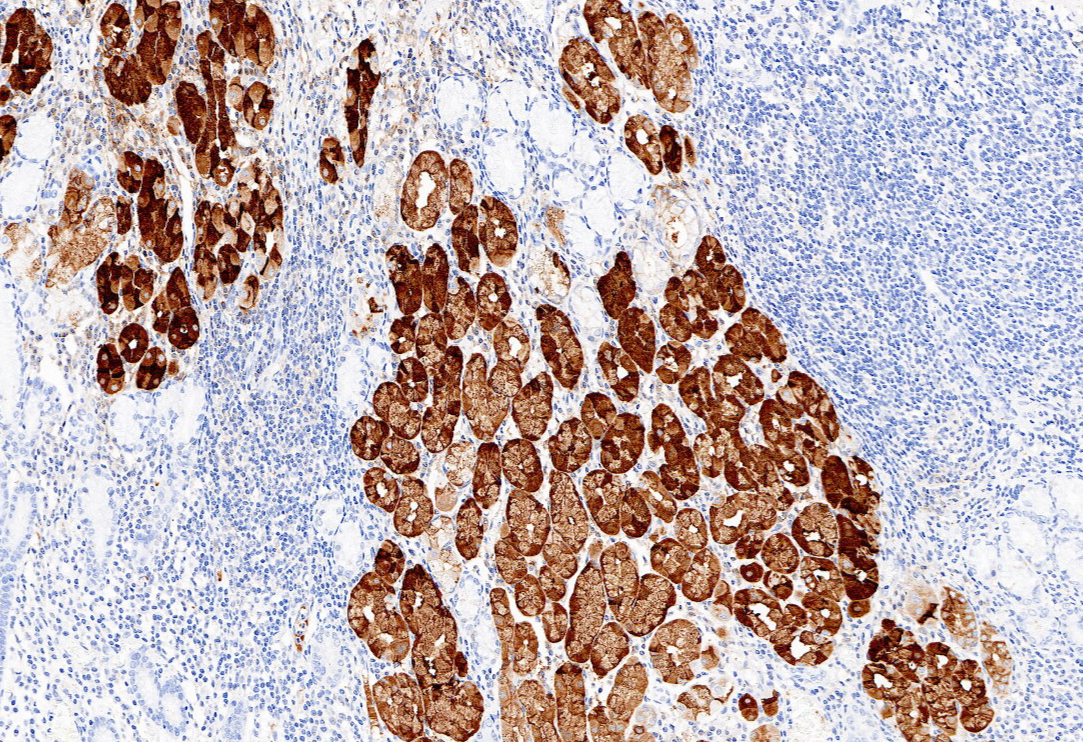

胃蛋白酶原Ⅰ(PepsinogenⅠ)主要由胃底腺的主細胞和黏液頸細胞分泌,當胃黏膜發生萎縮時,主細胞數量減少,Pepsinogen Ⅰ分泌減少。因此,Pepsinogen Ⅰ可在一定程度上反映胃黏膜的分泌功能和病理狀態,在胃癌及慢性萎縮性胃炎的診斷中具有重要的臨床意義。

| 克隆號 | 定位 | 陽性對照 | 修復條件 |

| 7G3 | 細胞漿 | 胃 | 高PH熱修復 |

胃石蠟組織,用Pepsinogen I染色,DAB顯色